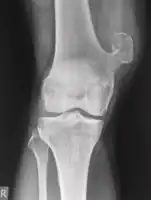

Medical imaging usually shows a well-defined wide-based bony growth on the surface of bone.[5] It can be pedunculated and irregular, giving it a "bizarre" appearance, and is not connected to underlying bone.[2]

X-ray hand, BPOP 2nd metacarpal -

X-ray hand, BPOP 2nd metacarpal (side view)